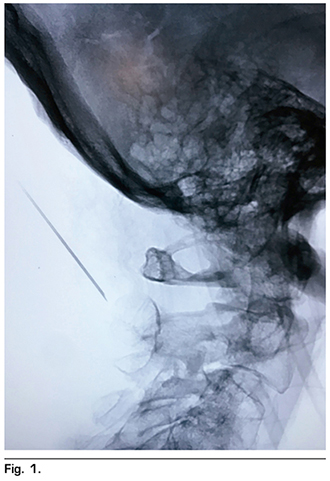

La técnica que se utilizó fue descrita por Racz y cols. (12), se localizaron mediante guía fluoroscópica a través de un arco C y en una posición anteroposterior las vértebras cervicales 1 y 2, posteriormente se rotó el equipo de arco en C a 90° para observar una proyección lateral, localizando las apófisis espinosas de las vértebras cervicales 1 y 2 (C-1 y C-2). Se eligió el punto de abordaje, localizado a 2 centímetros lateral izquierda de la protuberancia occipital mayor en la línea nucal superior, se infiltró piel cabelluda y tejido celular subcutáneo con lidocaína simple al 2 %. Posteriormente se introdujo una aguja espinal BD tipo Quincke 22 G 88 mm, en sentido cefalocaudal y lateromedial; de manera cuidadosa se avanzó a través de las capas fasciales musculares para evitar una lesión nerviosa o vascular (entre las que se encuentran la raíz nerviosa de C-1 o nervio suboccipital, raíz nerviosa de C-2 o tercer nervio occipital, el plexo cervical, la arteria cervical ascedente, la arteria o vena cervical profunda, y la arteria o vena vertebral) hasta hacer contacto con apófisis espinosa de C-2 (Figura 1); se retiró 2 mm y se aspiró para verificar punción inadvertida de vasos o duramadre. Una vez confirmado que no hubo salida de sangre o líquido cefalorraquídeo, se administraron 4 ml de medio de contraste no iónico, observando una difusión hacia la región occipital de forma triangular (triángulo formado por los músculos oblicuo mayor, oblicuo menor, recto posterior de la cabeza y el semiespinoso de la cabeza) (Figura 2). Ya corroborado el objetivo terapéutico, se aspiró nuevamente y se administraron 5 ml de bupivacaína (25 mg) con metilprednisolona no soluble (40 mg) aforados en solución salina hasta un total de volumen de 10 ml en el lado afectado, observando una adecuada disección de los planos musculares antes descritos en la imagen fluoroscópica. Se retiró aguja, se pasó a la paciente a recuperación sin incidentes, ni complicaciones.